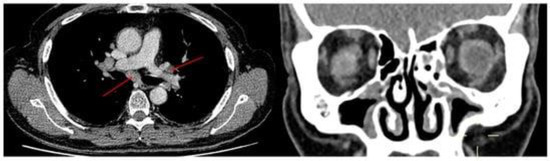

- Chan, R.; Kuo, C.R.; Lipworth, B. Low-Grade B Cell Lymphoproliferative Disorder Masquerading as Chronic Rhinosinusitis. Sinusitis 2021, 5, 1–4. [Google Scholar] [CrossRef]